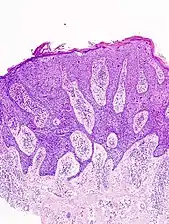

Invasive disease

In invasive SCC, tumor cells infiltrate through the basement membrane. The infiltrate can be somewhat difficult to detect in the early stages of invasion: however, additional indicators such as full thickness epidermal atypia and the involvement of hair follicles can be used to facilitate the diagnosis. Later stages of invasion are characterized by the formation of nests of atypical tumor cells in the dermis, often with a corresponding inflammatory infiltrate.[33]

Superficially invasive squamous cell carcinoma (SCCSI). These lesions often do not show the marked pleomorphism and atypical nuclei of SCC in situ, but demonstrate early keratinocyte invasion of the dermis.[33]

High magnification demonstrates the pleomorphism of the invading keratinocytes.[33]

Invasive nests with characteristic large celled centers. Ulceration (at left) is common in invasive SCC.